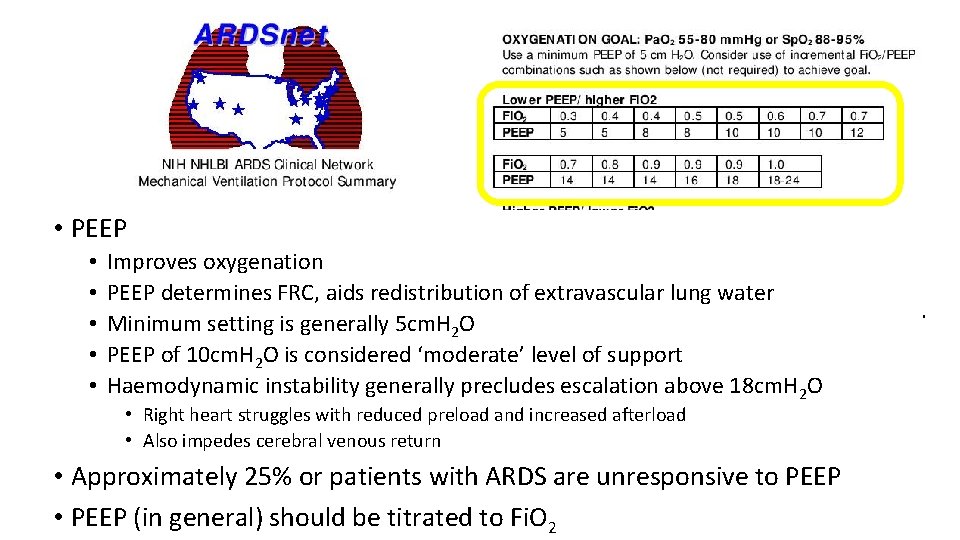

• PEEP • • • Improves oxygenation PEEP determines FRC, aids redistribution of extravascular lung water Minimum setting is generally 5 cm. H 2 O PEEP of 10 cm. H 2 O is considered ‘moderate’ level of support Haemodynamic instability generally precludes escalation above 18 cm. H 2 O • Right heart struggles with reduced preload and increased afterload • Also impedes cerebral venous return • Approximately 25% or patients with ARDS are unresponsive to PEEP • PEEP (in general) should be titrated to Fi. O 2